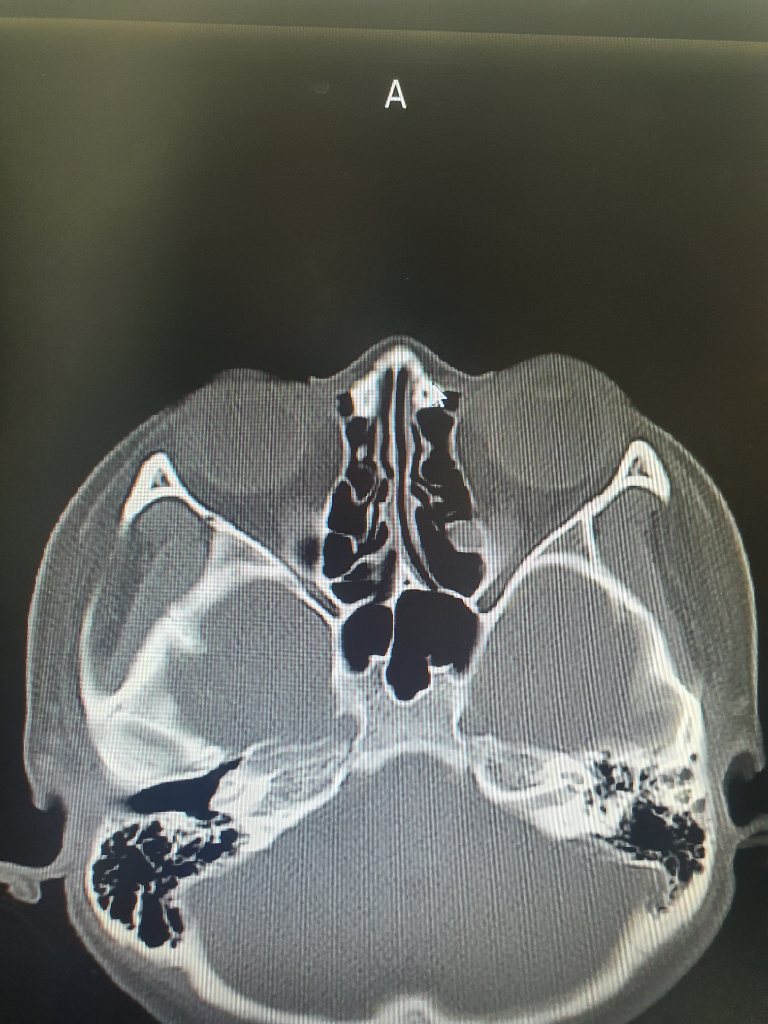

Ct찍은 사진보면 코뼈 재골절된건가요?

제가 작년10월에 오른쪽 코뼈가 부러져서 정복술 수술을받았습니다.

그러고 엊그제 서랍장 손잡이에 부러진곳 정중앙을 부딪혀 코가 또부러진건지 걱정되어 오늘 병원에서 ct및 3dct를 찍었습니다. 선생님께서는 골절은 안보이고 그냥 타박상같다고, 혹시 미세골절이 있더라도 수술할정도는 아니라서 걱정 안해도된다고하셨습니다. 전 처음 코뼈수술한 대학병원에 다시가봐야할지 고민이 되어서요. 사진상 골절소견은 보이지않나요?

이 세사진으로 코뼈 골절을 진단하기는 매우 어렵겠습니다.

해당 병원에 판독지 등을 요청해 보시는 것이 좋겠습니다.

• 올리신 사진의 몇 장 가지고 확실하게 판단하기는 어렵습니다만, 적어도 올리신 사진의 소견에는 코뼈 골절이 따로 보이지 않습니다. 걱정되신다면 수술 받으신 병원에서 재차 진료를 받아보는 것도 괜찮은 방법입니다만 크게 소견에 차이가 있지는 않을 것 같습니다.